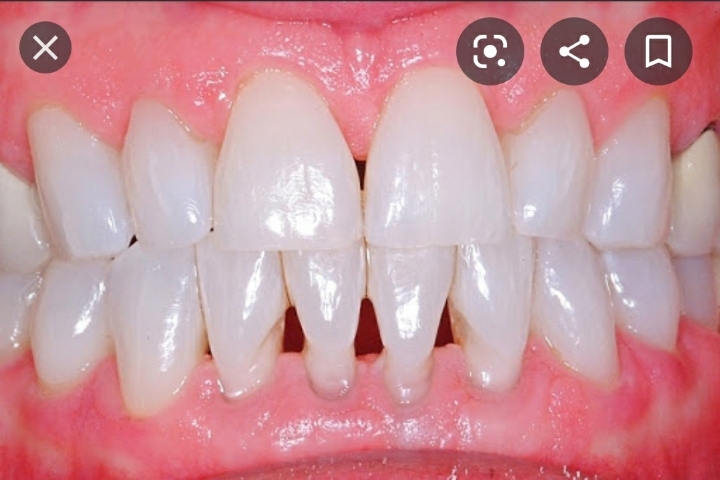

그럼 이렇게 블랙 트라이앵글이 생김

문제는 치석이 쌓이면 더 내려앉아서 뿌리 다 보임..

그럼 내려앉은 잇몸은 어떻게 다시 올리냐??

방법 없음.

하얀 레진으로 치아 밑동을 감싸서 안시리게 하거나(그래도 잇몸 더 내려감)

아니면 입천장을 얇게 포떠서 잇몸에 덧대거나(그래도 다시 잇몸 내려감)

내려간 잇몸은 다시 안올라옴.